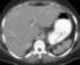

Abnormal left upper quadrant abdominal gas collection

Acute pancreatitis (AP) is a sudden inflammation of the pancreas. Causes in order of frequency include: 1) a gallstone impacted in the common bile duct beyond the point where the pancreatic duct joins it; 2) heavy alcohol use; 3) systemic disease; 4) trauma; 5) and, in minors, mumps. [Source: Wikipedia ]